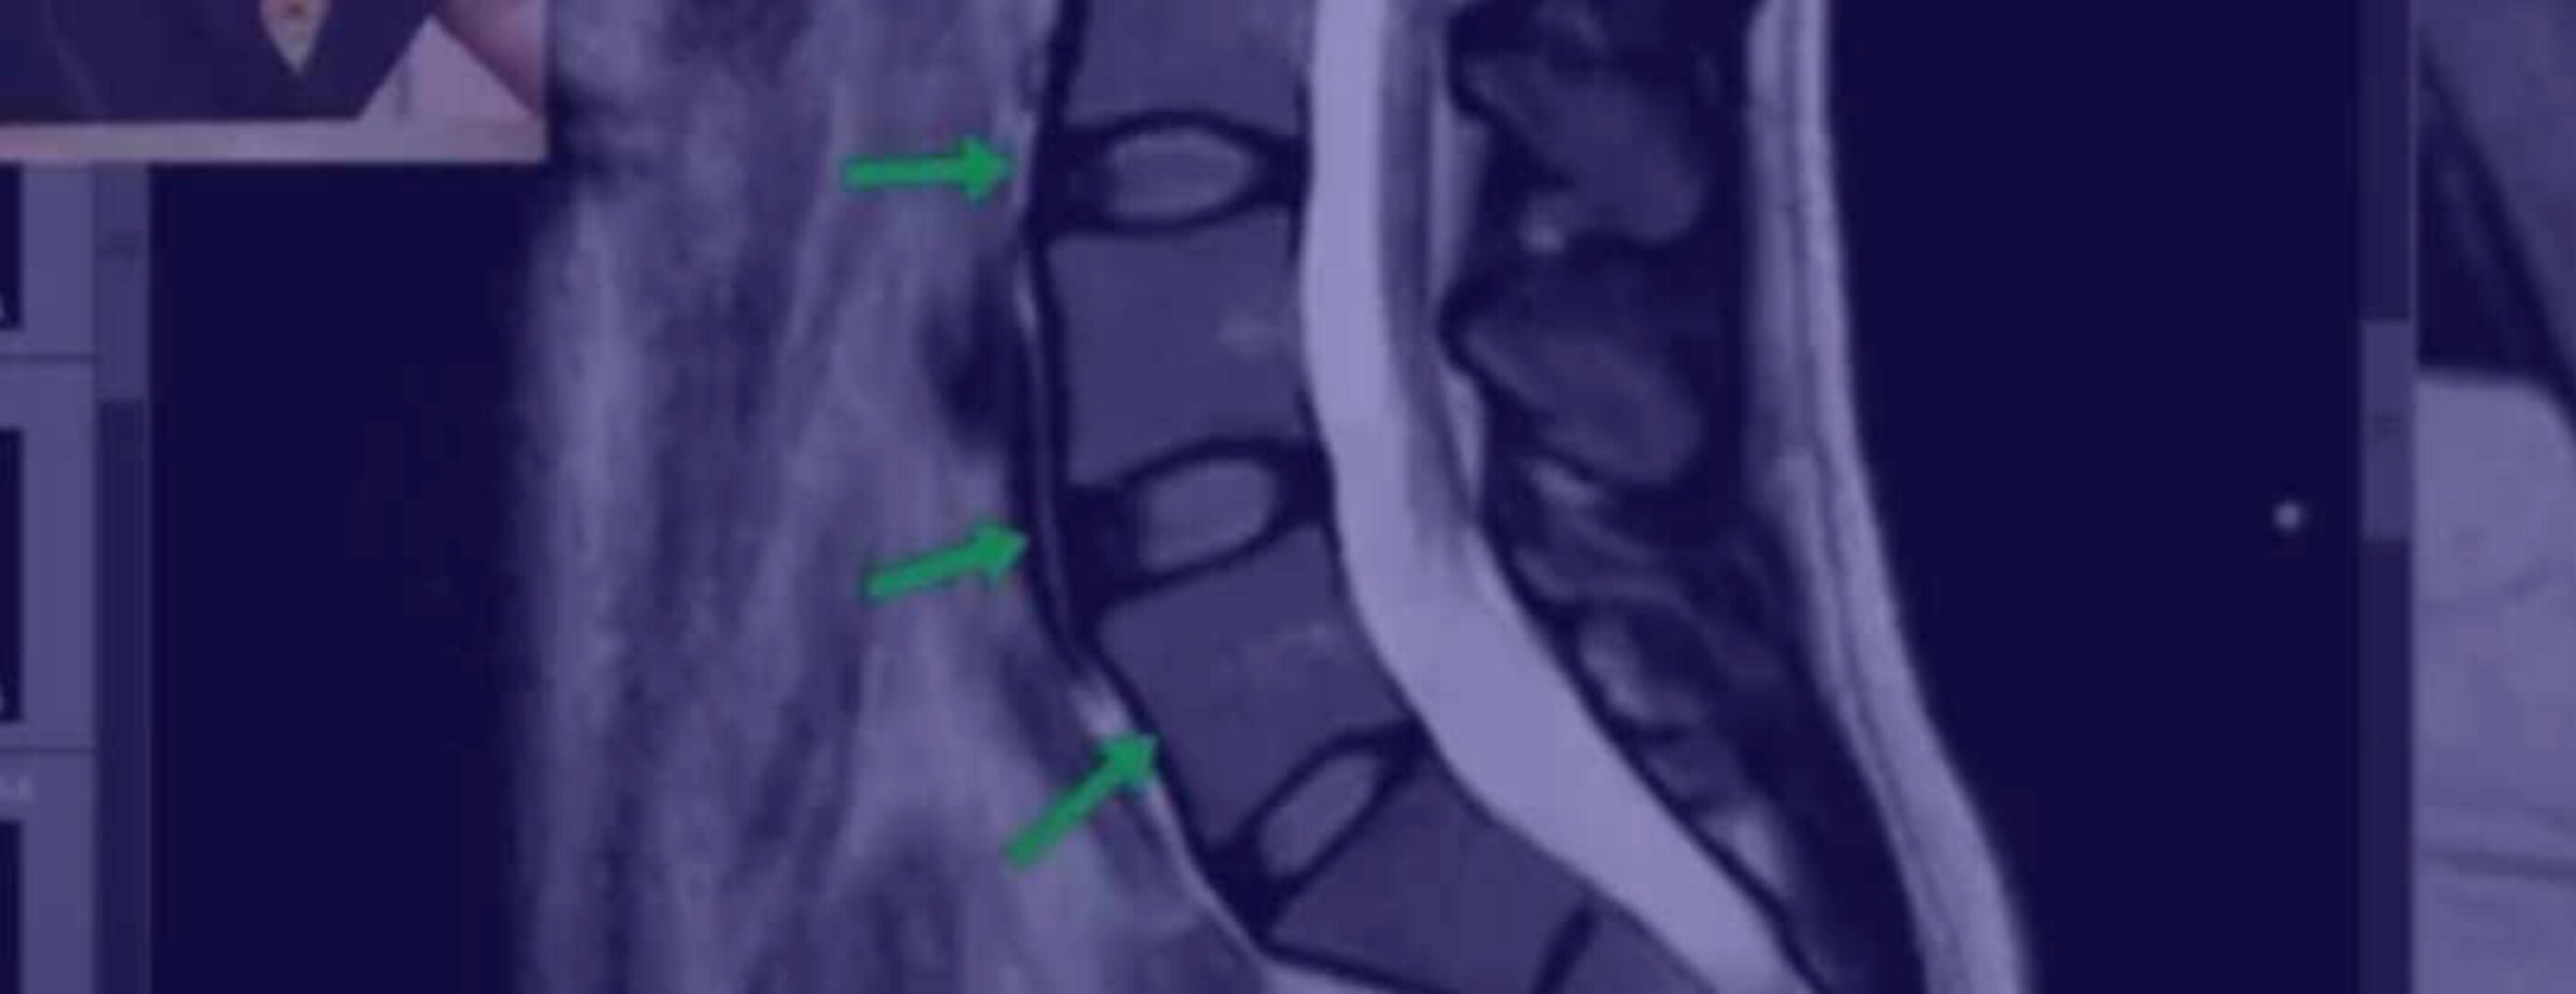

На примере большого количества снимков вы узнаете, как выглядит грыжа, протрузия, стеноз канала, сдавление корешков, жировая дегенерация мышц, как мышцы спазмируются при грыже, откуда берется поясничный прострел и многое другое. Если вы будете постоянно смотреть МРТ своих пациентов и сравнивать